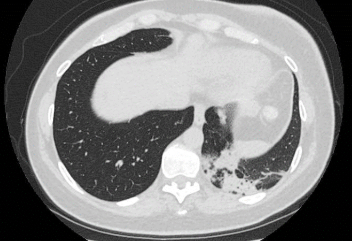

De hyppigste fund er subpleurale eller peribronkiale diffuse alveolære konsolideringer, ofte multiple og forekommende i flere lapper, der kan progrediere, regrediere og migrere over tid. Konsolideringerne kan være unilaterale og bilaterale og kan ses i alle lungezoner, men midt-zone og basale zoner er hyppigst. Der kan ses nodulære forandringer, typisk peribronkialt og peribronkiolært.

Figur 1 og 2 viser eksempel på hhv. revers halo-tegn og subpleurale konsolideringer på HRCT.

Figur 2: Aksialt HRCT-billede med subpleurale konsolideringer og perilobulært mønster i venstre underlap.